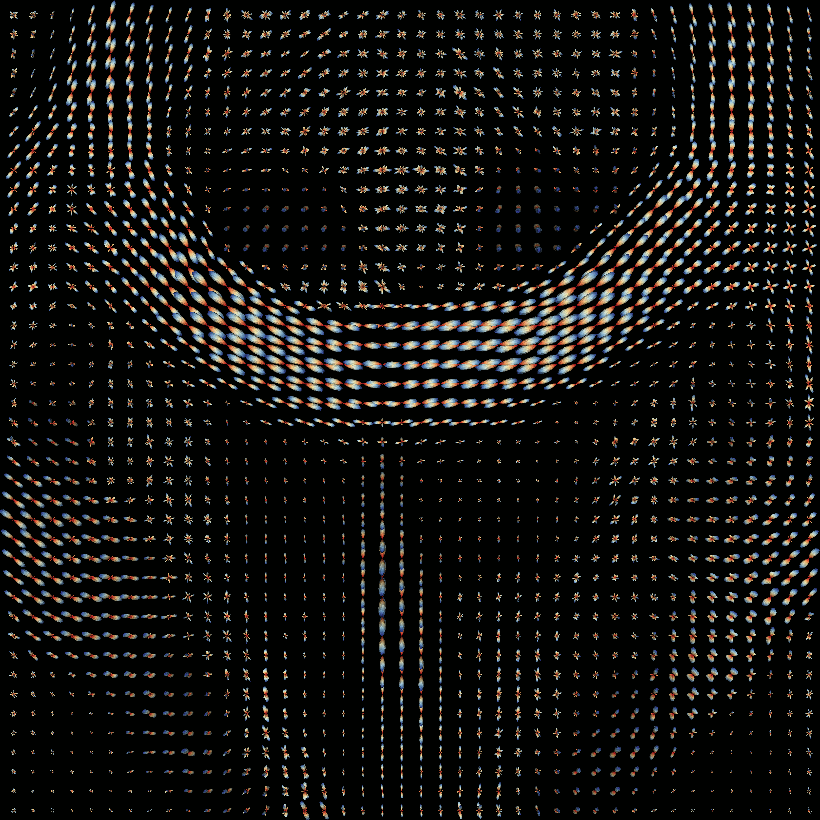

Analysis - Reconstruction

08-10 Tensor reconstruction

11-12 fODF reconstruction

13-14 Tractographies

FA

AD

RD...

CSD PEAKS

NUFO